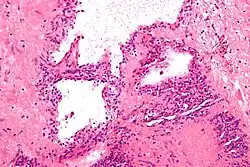

| Micrograph showing a pancreatic serous cystadenoma. H&E stain. | |